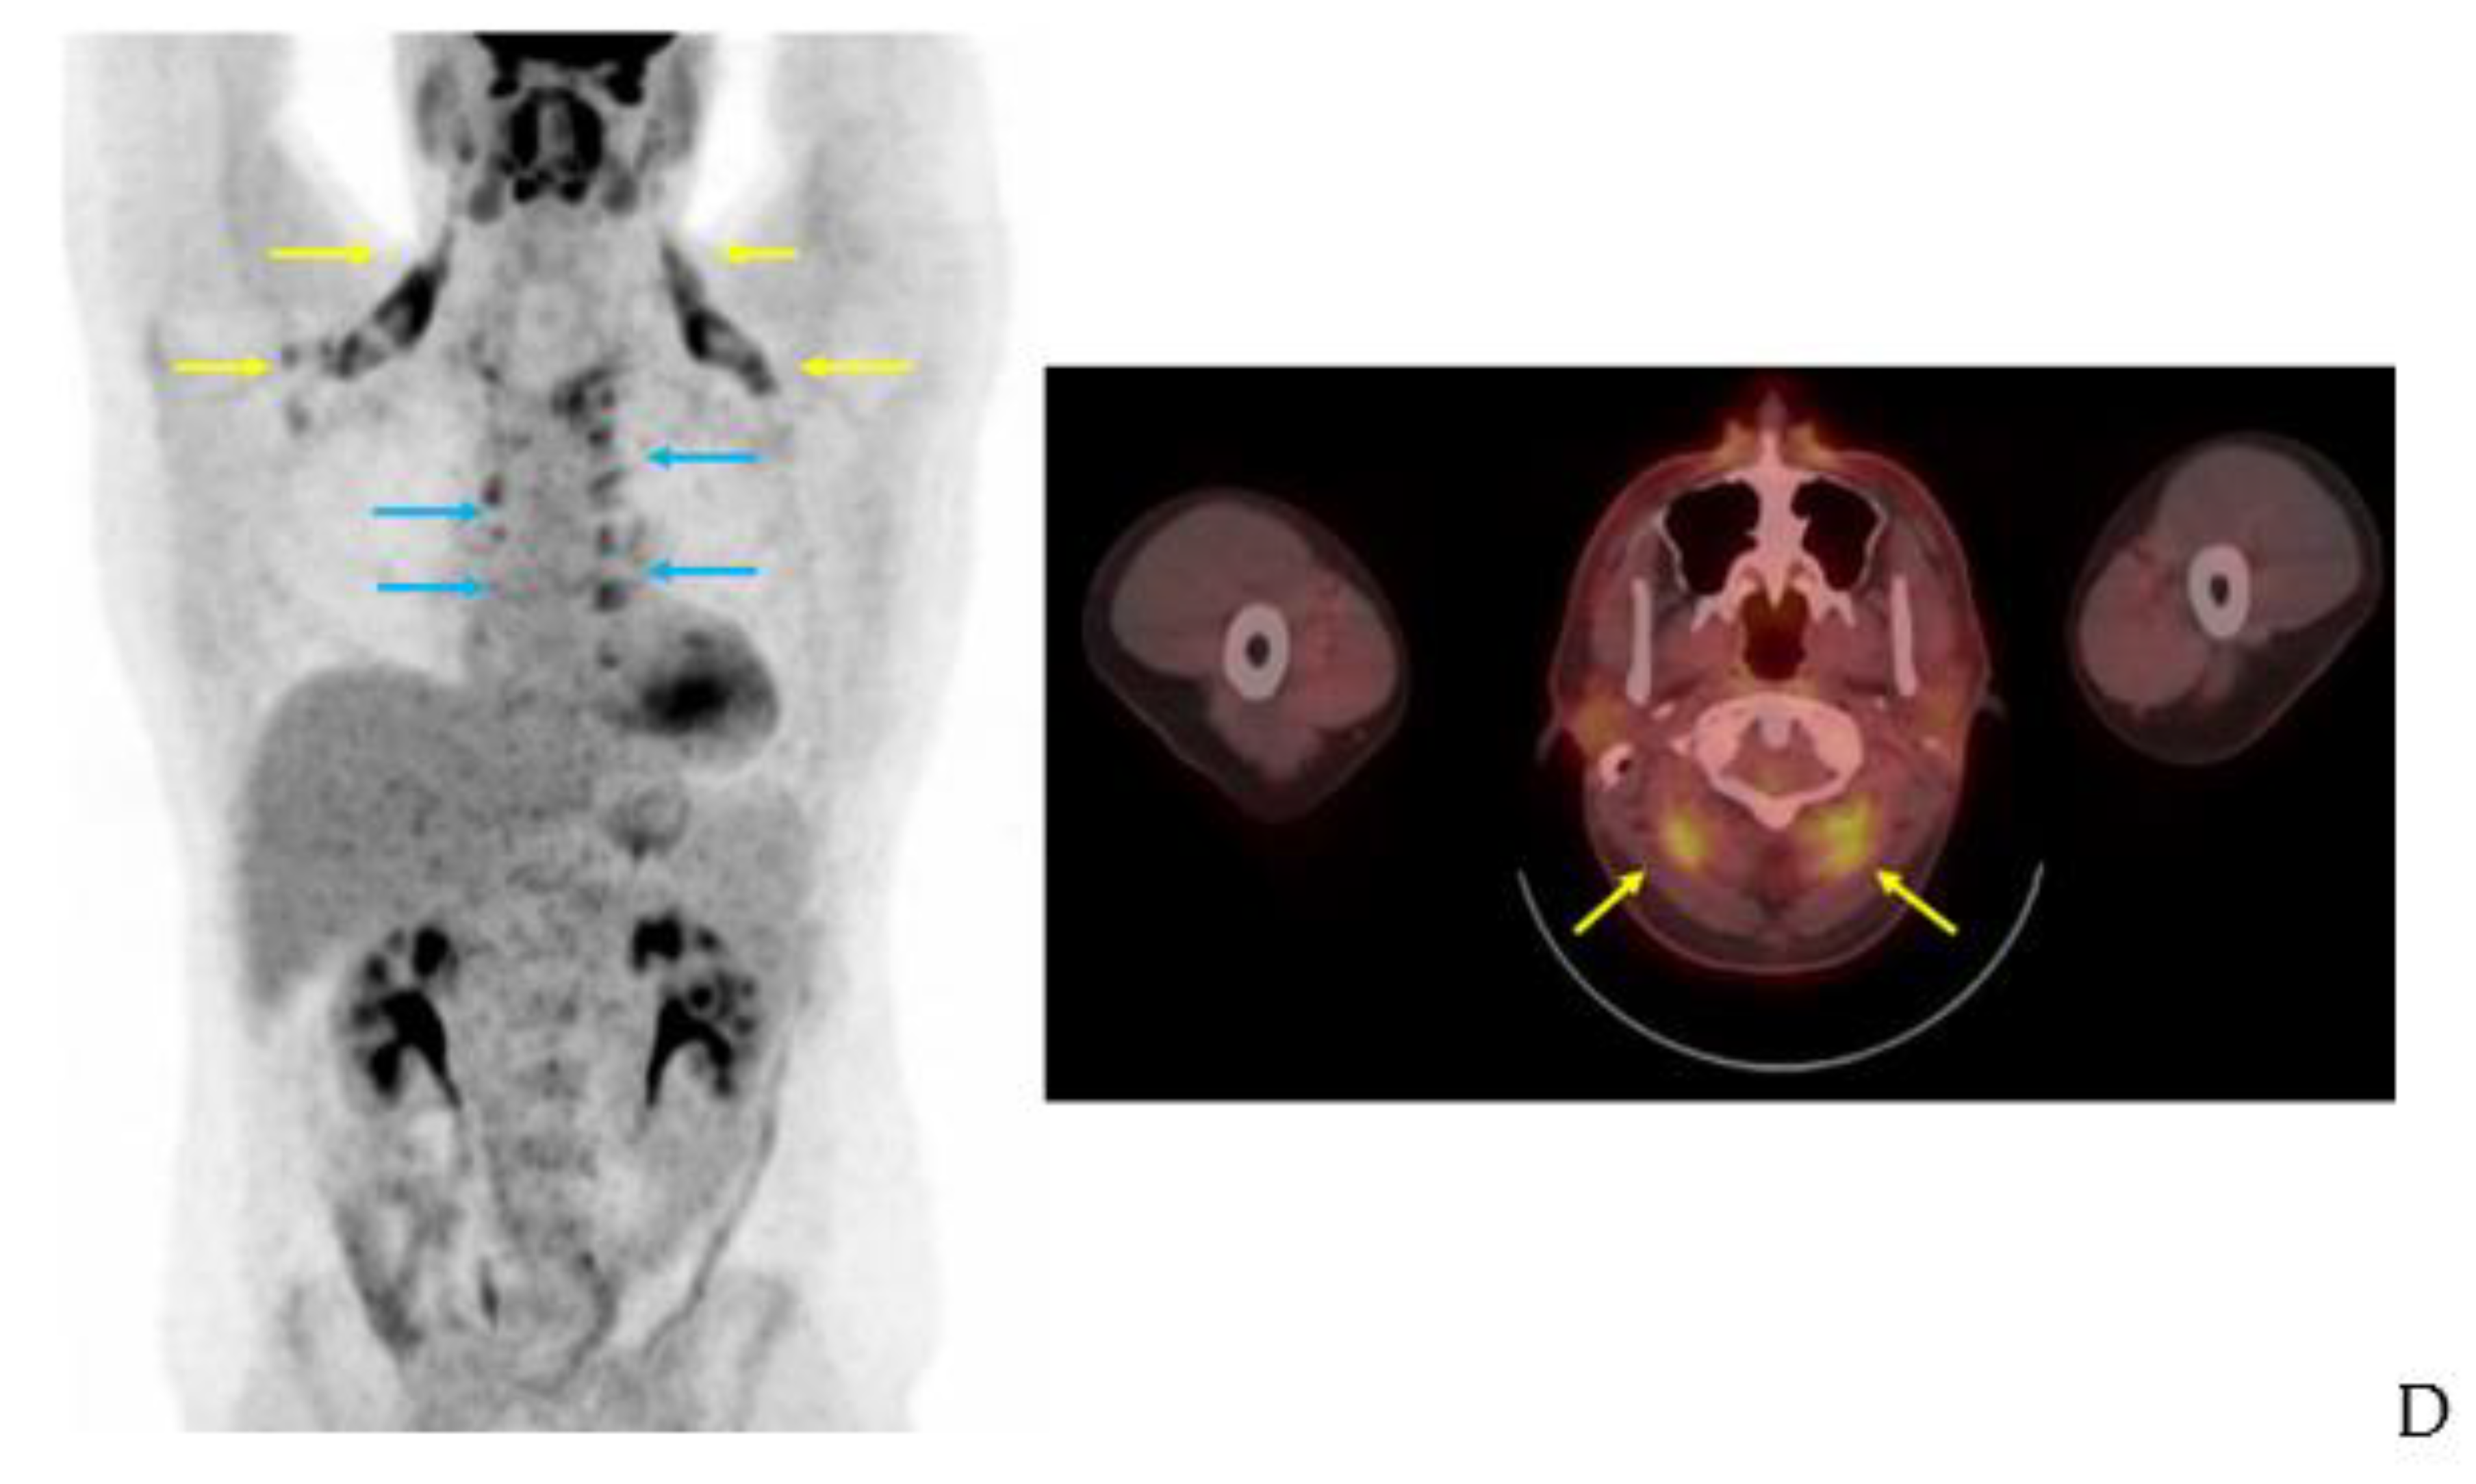

BAT is detected with other clinical and investigational radiotracers. 123I-metaiodobenzylguanidine (MIBG) SPECT/CT localizes sympathetic innervation by using a labeled norepinephrine analogue [75]. MIBG localizes BAT with similar sensitivity to FDG-PET/CT but is less temperature dependent [9,75,76]. The 11C PET tracer and norepinephrine analog 11C-meta-hydroxyephedrin has demonstrated sensitivity to BAT at thermoneutral conditions and its activity correlates with FDG uptake with acute cold in humans [77]. The commonly used SPECT/CT tracer 99mTc-methoxyisobutylisonitrile (MIBI), which localizes to tissues with high mitochondrial density, detects BAT in a non-temperature dependent manner as shown in an example from our clinical practice (Figure 9) [76,78]. 15O-labeled water PET/CT has been used in this setting to measure blood flow, which provides data to estimate tissue-specific metabolic rate using arterial oxygenation and known oxygen extraction fractions [77]. Din and colleagues combined 15O-labeled water PET/CT with inhaled 15O administration to directly measure tissue metabolic rate in humans [79]. The short (2 min) half-life of 15O allows for repeat PET scanning with another tracer on the same day [77,79]. Investigational radiotracer currently include the mitochondrial outer membrane translocator protein, visualized with 18F-FEPPA PET/CT and 11C-PBR28 PET/CT, the cannabinoid type 1 receptor, visualized with 18F-FMPEP-d2 PET/CT [80,81,82,83], and PD-L1, visualized with radiolabeled antibodies [84,85].

Figure 9.

99mTc-MIBI uptake in iBAT on a clinical scan. Supraclavicular BAT uptake shown coronal and axial fused 99mTc-MIBI-SPECT/CT (yellow arrows). Salivary gland uptake (white arrows) is normal.